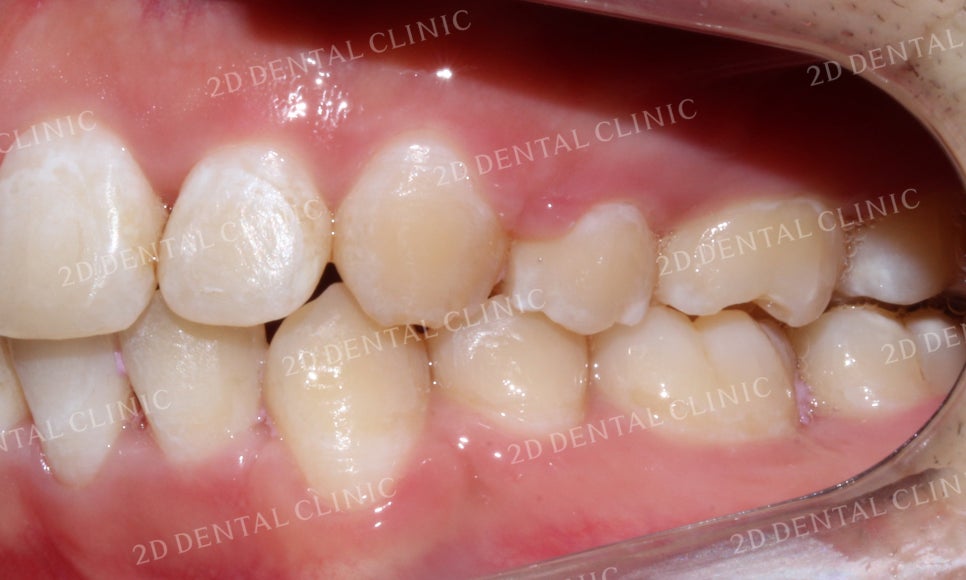

좌측 구치부의 교합 시 모습입니다.

발달한 상악과 미약한 하악의

교합으로 하악이 과도하게

물리는 것을 확인할 수 있습니다.